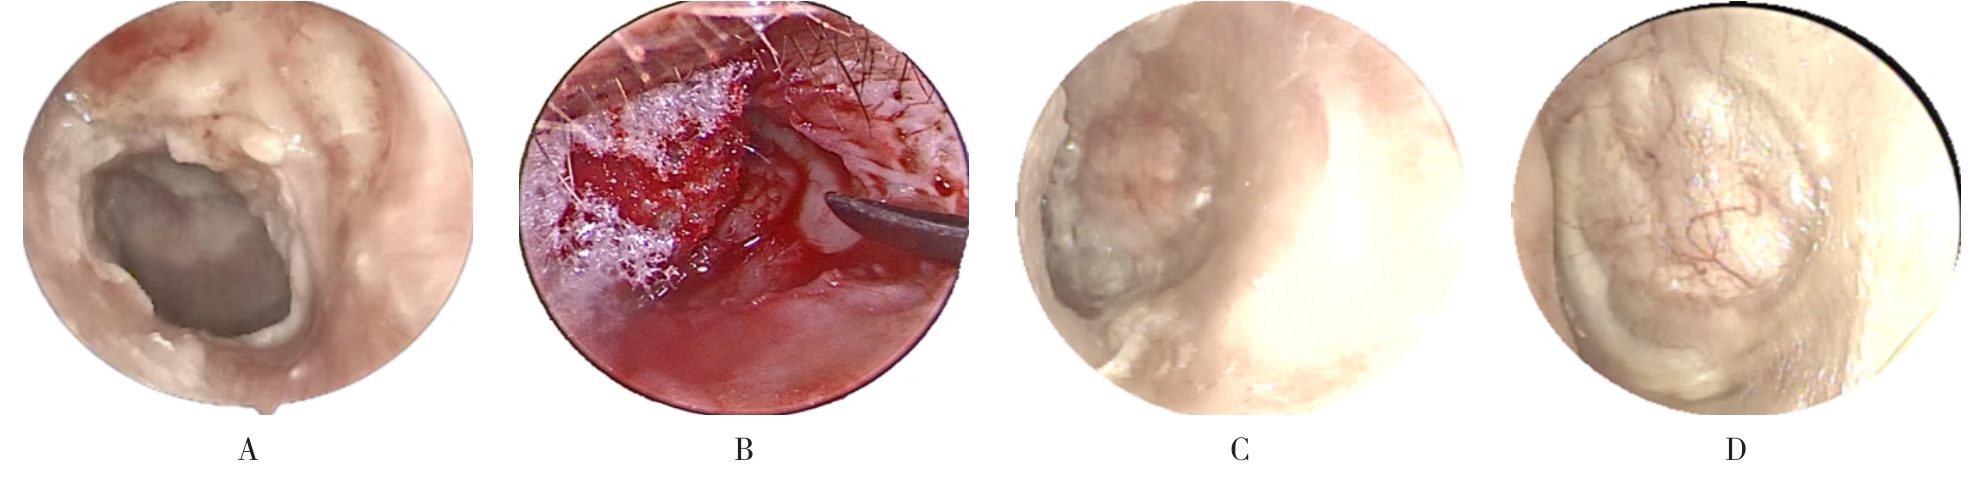

摘要:目的 分析医用生物蛋白胶应用于耳内镜下鼓膜修补术的临床疗效。方法 回顾性分析2022年10月-2023年10月该院收治的60例单纯鼓膜穿孔患者的临床资料,根据手术方法不同,将患者分为研究组和对照组,各30例。研究组术中使用医用生物蛋白胶粘合残余鼓膜和修补材料;对照组术中采用明胶海绵覆盖修补鼓膜。观察两组患者术后的鼓膜愈合情况(鼓膜愈合率、愈合时间、干耳时间和外耳道上下径)和并发症发生情况;于手术前后,采用纯音测听法(500、1 000、2 000、4 000 Hz),测量两组患者气导阈值,观察听力改善程度;采用视觉模拟评分法(VAS)评分,评估患者术后疼痛程度。结果 两组患者术后鼓膜愈合率、愈合时间、外耳道上下径和并发症发生率比较,差异均无统计学意义(P > 0.05)。研究组术后平均气导听阈明显低于对照组,差异有统计学意义(P < 0.05)。研究组术后干耳时间短于对照组,术后第1天疼痛VAS评分明显低于对照组,差异均有统计学意义(P < 0.05)。结论 医用生物蛋白胶应用于耳内镜下鼓膜修补术,可有效地降低气导听阈,缩短干耳时间,减轻患者疼痛,且不增加并发症发生率,值得临床推广应用。